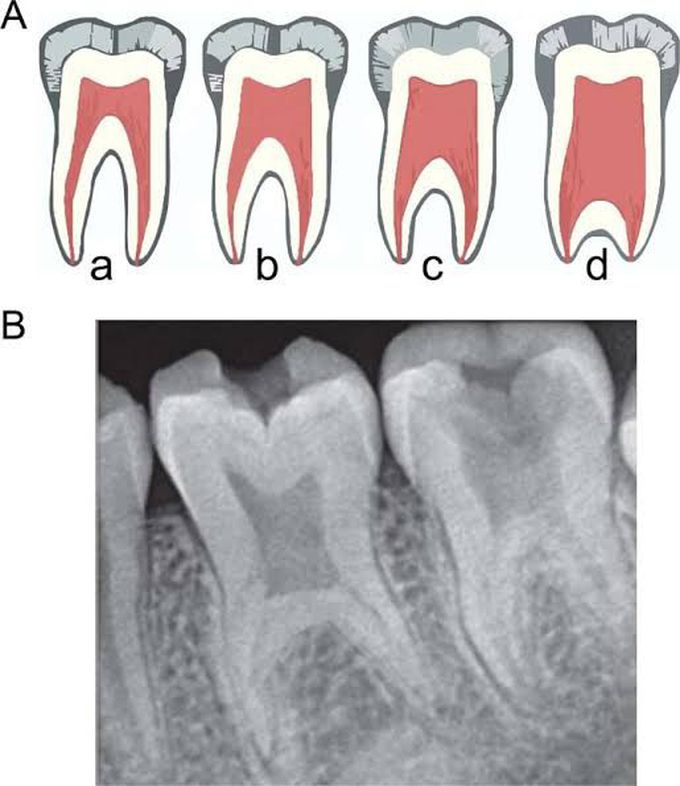

Taurodontism is a developmental disturbance of a tooth in which body is enlarged at the expense of the roots. An enlarged pulp chamber, apical displacement of the pulpal floor and lack of constriction at the cementoenamel junction are the characteristic features. It appears most frequently as an isolated anomaly.